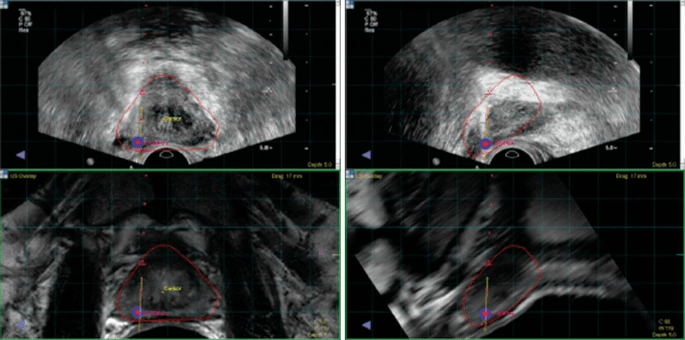

澳大利亞和新西蘭的一組研究人員發(fā)現(xiàn),MRI掃描比新的前列腺特異性PET/CT掃描技術(shù)更準(zhǔn)確地檢測前列腺癌。

前列腺特異性膜抗原(PSMA) PET/CT掃描于2020年獲得美國FDA批準(zhǔn),使用放射性染料“點(diǎn)亮”前列腺癌細(xì)胞表面的PSMA區(qū)域。它們目前被用于治療前列腺癌,因?yàn)樗鼈兛梢詼?zhǔn)確地測量疾病的進(jìn)展或復(fù)發(fā)。因此,在這項(xiàng)試驗(yàn)中,研究人員開始研究它們是否也可以用于診斷前列腺癌。

PEDAL試驗(yàn)招募了來自5個(gè)醫(yī)院組的240名有前列腺癌風(fēng)險(xiǎn)的患者。每個(gè)患者都接受了MRI掃描和PSMA PET/CT掃描。如果影像顯示前列腺癌的存在,則由患者的泌尿科醫(yī)生進(jìn)行活檢。

磁共振掃描發(fā)現(xiàn)異常141例,PSMA PET/CT掃描發(fā)現(xiàn)異常198例。181例患者(75%)接受了前列腺活檢,其中82例患者被發(fā)現(xiàn)有臨床意義的前列腺癌。

由于每個(gè)病人都接受了兩種類型的掃描,研究人員可以評估哪種類型能更準(zhǔn)確地檢測出那些患有前列腺癌的病人。研究人員發(fā)現(xiàn),在檢測任何級別的前列腺癌時(shí),MRI掃描比PSMA PET掃描更準(zhǔn)確(MRI為0.75%,PSMA PET為0.62%)。

澳大利亞墨爾本圣文森特醫(yī)院泌尿腫瘤顧問醫(yī)師王立明(Lih-Ming Wong)副教授領(lǐng)導(dǎo)了這個(gè)研究小組。他說:“我們的分析發(fā)現(xiàn),在檢測任何級別的前列腺癌方面,核磁共振掃描比PSMA-PET更有效。當(dāng)我們只觀察臨床意義重大的前列腺癌時(shí),在準(zhǔn)確性上沒有差異。由于這項(xiàng)研究是第一個(gè)探索使用PSMA-PET診斷前列腺癌的研究之一,我們?nèi)栽趯W(xué)習(xí)和調(diào)整如何在這種情況下改善使用PSMA-PET。

盡管檢測閾值將隨著診斷用途的發(fā)展而微調(diào),但Wong教授認(rèn)為,這項(xiàng)試驗(yàn)對臨床醫(yī)生有重要的教訓(xùn)。

他說:“這項(xiàng)研究證實(shí),活檢前檢測的現(xiàn)有‘金標(biāo)準(zhǔn)’——核磁共振成像——確實(shí)是一個(gè)很高的基準(zhǔn)。即使經(jīng)過微調(diào),我們懷疑PSMA PET/CT仍不能取代MRI作為前列腺癌檢測的主要方法。但未來它可能會(huì)作為核磁共振成像的輔助手段,或用于不適合核磁共振成像的人,或作為對適當(dāng)選擇的患者進(jìn)行“診斷和分期”掃描的單一組合。